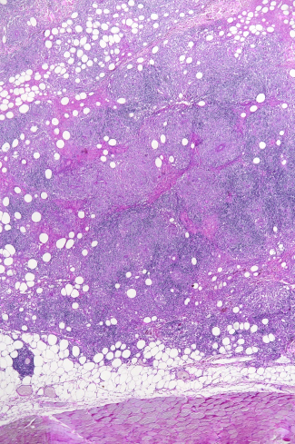

Das Krankheitsbild von Balu ist sehr unüblich. Nicht zuletzt muss selbst bei einem so jungen Hund auch an Hautkrebs gedacht werden, weshalb wir uns zur Entnahme von Gewebeproben unter einer kurzen Narkose entscheiden. Der Gewebebefund ist ebenfalls unüblich: Der Pathologe diagnostiziert einen bestimmten Typ einer entzündlichen Veränderung der Haut (Dermatitis). Eine erweiterte Gewebeuntersuchung weist nach, dass der Hund nicht an einer Leishmaniose leidet - diese parasitäre Krankheit könnte nämlich ein ähnliches Bild verursachen. Abschliessend wird also die Diagnose einer "pyogranulomatösen Dermatitis/Adnexitis" gestellt.

Beim sogenannten "sterilen pyogranulomatösen Syndrom" des Hundes handelt es sich um eine selten auftretende Entzündung der Haut, deren Ursache nicht geklärt ist. Das Immunsystem beginnt, körpereigene Strukturen anzugreifen, was zu Knoten, Haarausfall, nässenden Schwellungen und Geschwüren führen kann. Betroffene Hunde können auch systemische Zeichen wie Lethargie und Appetitverlust zeigen; die Diagnose kann nur über Gewebeproben gestellt werden. Da die Ursache des Problems unklar ist, bleibt keine andere Möglichkeit, als das Immunsystem mit Medikamenten davon abzuhalten, den Körper anzugreifen.

Wir danken Dr. Dr. U. Hetzel vom Institut für Veterinärpathologie der Uni Zürich herzlich für die mikroskopischen Aufnahmen.